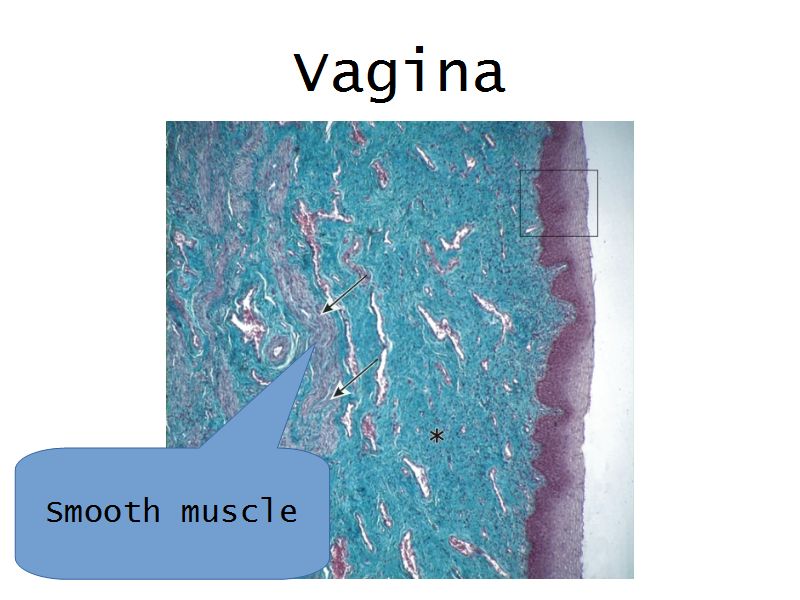

Vagina

Slide 90

Vagina

- Fibromuscular tube with 3 layers

- Inner mucosa

- Middle muscle layer

- External adventitia

Fibro = fibrous tissue

Muscular = muscle tissue

Tube = epithelium

Muscle layer

- Thin inner circular

- Thick outer longitudinal

- External orifice ring of skeletal muscle